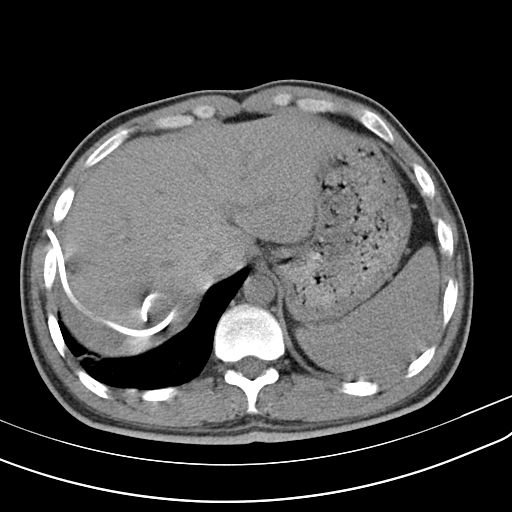

CT:双肺多发空洞、气囊、结节,病灶以胸膜下为主,见实变,胸腔积液。肝脓肿。

CT也提示脓毒肺栓塞!

这个患者的特点是肺空洞,肝脓肿!肝脓肿的存在,大大缩小了诊断范围,缩小了细菌范围!肺CT提示脓毒肺栓塞,并且同时存在肝脓肿,绝大多数都是肺炎克雷伯杆菌,不是金葡菌,真菌更是少见!